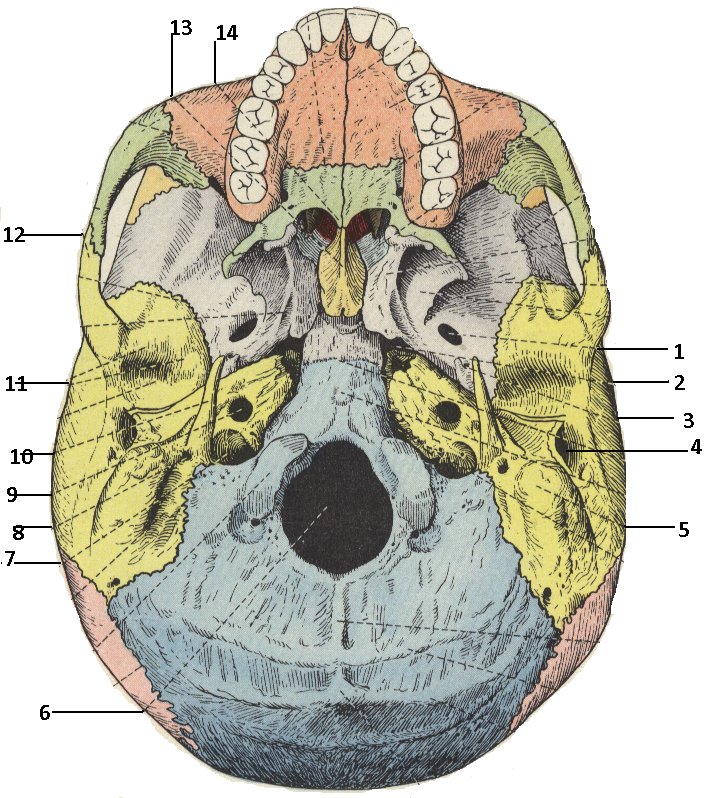

Анатомические детали: Фотографии топографии черепа с нижнего вида

Раздел: Альбом идей